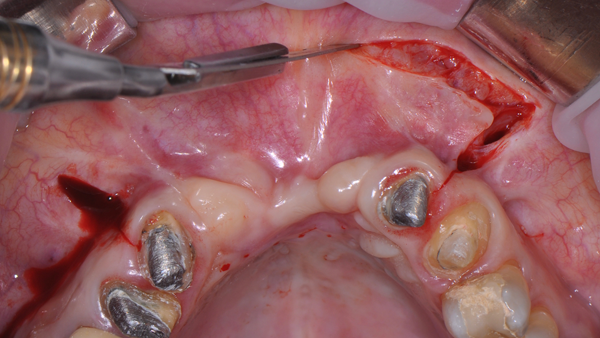

Foi utilizada uma membrana de politetrafl uoretileno denso (PTFE-d) reforçada com titânio (Cytoplast Ti250PS 20 mm x 25 mm, Osteogenics Biomedical) e osso heterógeno bovino (Lumina Porous, Critéria Biomateriais). O desenho do retalho invertido de base palatina (descrito anteriormente) foi escolhido para garantir fechamento após o procedimento de enxerto ósseo, apesar da dimensão aumentada da crista. Após o acesso ósseo, a membrana foi fixada com parafusos na região palatina (Figura 6) e o leito receptor foi preparado com penetrações múltiplas na cortical, usando uma pequena fresa (Figura 7).

O enxerto ósseo heterógeno foi acomodado no leito receptor e coberto com a membrana Cytoplast reforçada com titânio (Figura 8), que foi estabilizada com parafusos de fixação (Kit GBR, NeoBiotech), Figura 9.